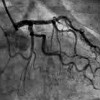

Ангиография артерий щитовидной железы

Ангиография артерий щитовидной железы представляет собой метод рентгенологического сканирования сосудов железистого органа с введением контрастного вещества. Исследование назначено при тиреотоксикозе, подозрении на коллоидный зоб, фолликулярную аденому, рак щитовидной железы. Для выполнения манипуляции врач вводит контраст в заданный объем через катетер, после чего он делает несколько рентгеновских снимков. Специалист оценивает характер кровоснабжения - центральный, периферический или смешанный, выявляет локальную извилистость артерий. Стоимость варьируется в зависимости от выбранного контраста, сложности выполнения (стандартная ангиография или КТ).